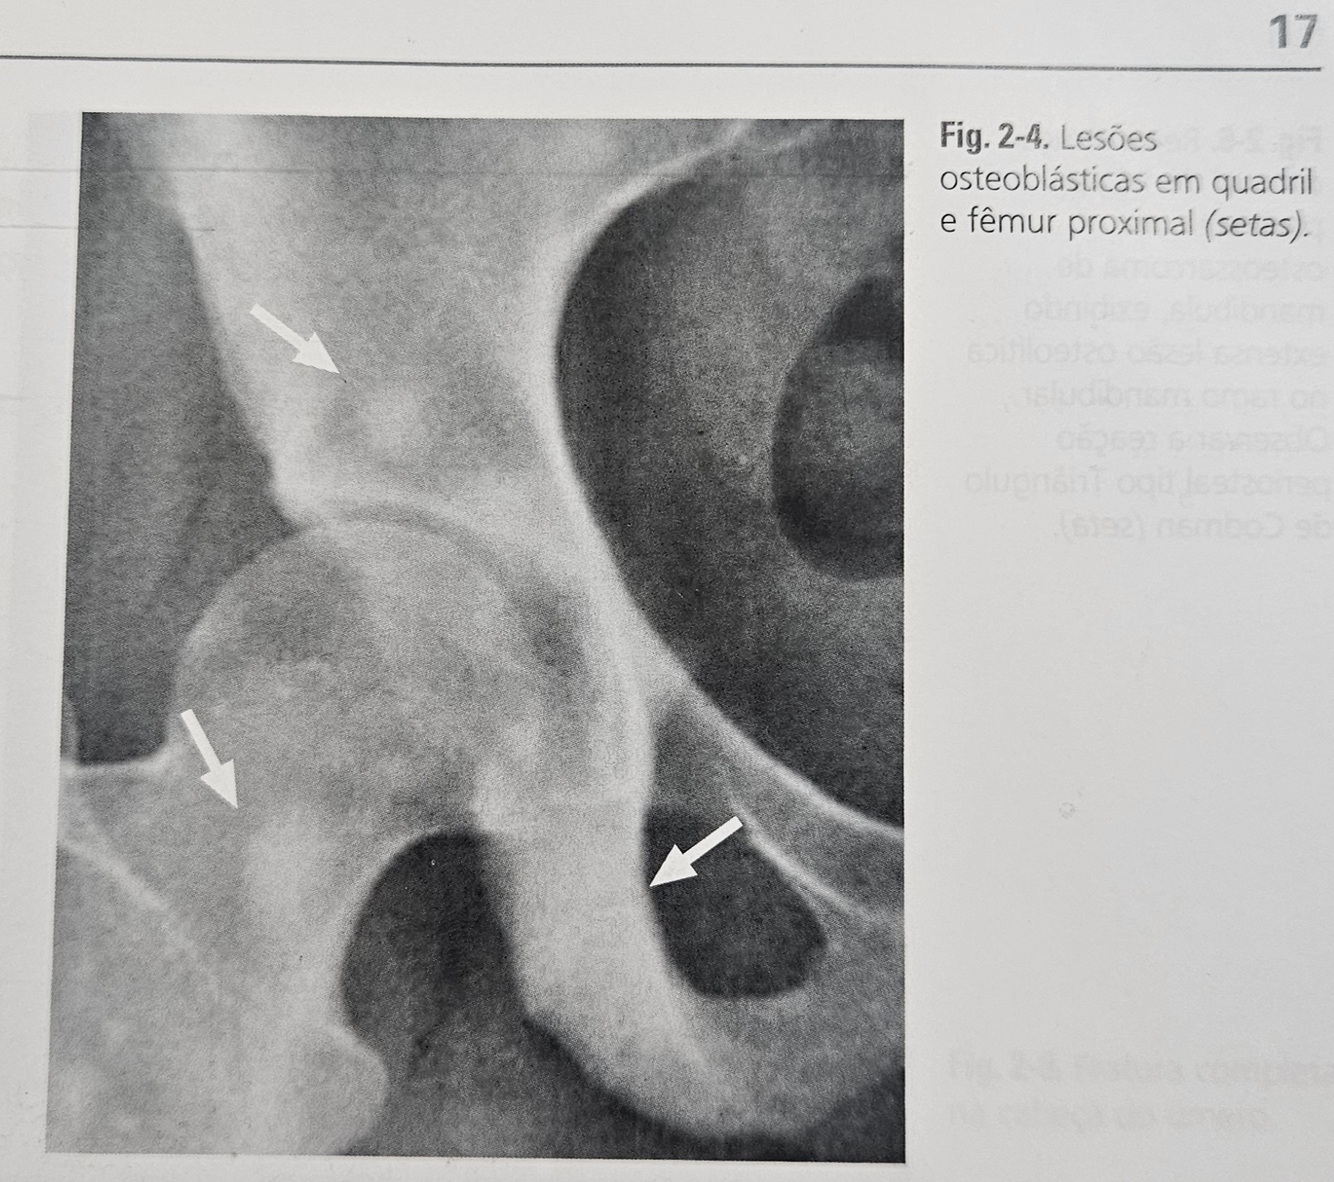

O que você entende por LESÕES OSTEOBLASTICAS?

São LESÕES formadoras de tecido anômalo, patológico, apresentando-se com áreas de maior densidade (hiperdensa) radiografica.